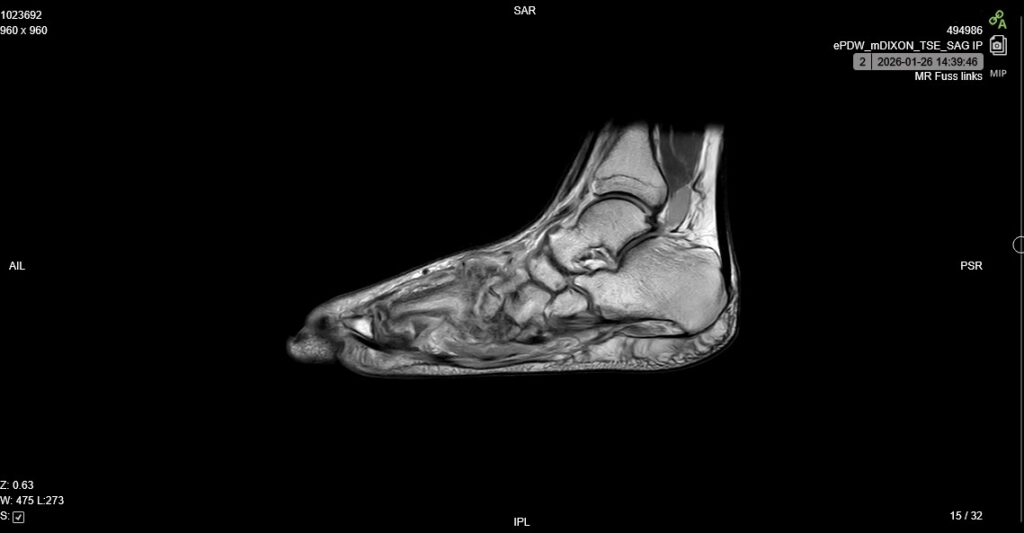

Die Prozedur im MRT-Zentrum ist mir mittlerweile bestens bekannt; erst im Oktober 2025 lag ich für denselben Fuß in dieser Röhre. Das übliche Protokoll: Schuhe ausziehen, alle Gegenstände aus den Taschen leeren, Schmuck und Ketten ablegen und dann ab ins MRT.

Diesmal gab es eine kleine Abweichung zur Routine: Man spritzte mir Kontrastmittel, um die Entzündungsprozesse im Fuß besser sichtbar zu machen. Ansonsten verlief die Untersuchung ohne besondere Vorkommnisse.

Nun heißt es: Warten. Während man die Bilder oft schon am selben Tag digital einsehen kann, ist der schriftliche Befundbericht meist erst am nächsten Tag online verfügbar. Und auch wenn ich mir die Aufnahmen neugierig anschaue – da ich kein Radiologe bin, bleibt das Ganze für mich natürlich ein Buch mit sieben Siegeln.